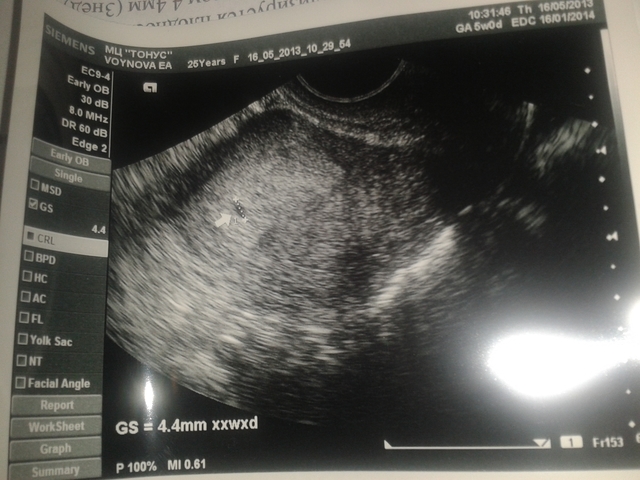

У нас получилось! Я беременна!Всем привет! !! Я ТЕПЕРЬ ТОЖЕ БЕРЕМЕНЯШКА!!! Сегодня была на узи срок 3 недельки, все хорошо, теперь буду отдыхать и наслаждаться прекрасной беременностью)))